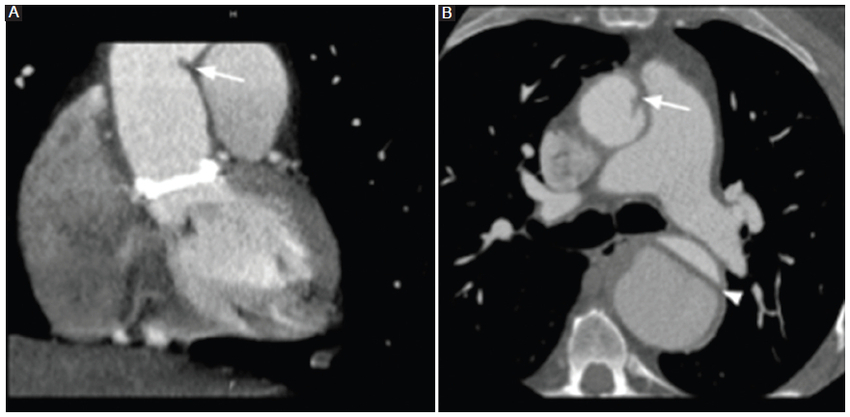

La fase sin contraste es de vital importancia para diferenciar las estructuras posquirúrgicas hiperdensas normales de las posibles complicaciones, como son la extravasación del material de contraste y los pseudoaneurismas. El dacrón es el material empleado en las prótesis y se observa de bordes redondeados, paredes lisas y ligeramente hiperdenso en las fases sin contraste intravenoso, lo cual puede simular un pseudoaneurisma. Este último se diferencia por su presentación típica en forma de lesiones hipodensas o isodensas en las imágenes sin contraste (Fig. 8) (3,4,5,6,7,8.

Otro dato a tener en cuenta son las tiras de fieltro que pueden verse alrededor del injerto, como en los sitios de colocación de la cánula arterial, al igual que el lugar de la anastomosis de la arteria coronaria (técnica del botón) (Fig. 9). Estas tiras también se observan espontáneamente densas en las fases sin contraste, pudiendo asemejar extravasación del contraste o un pseudoaneurisma (Fig. 10) (8. Otra manera de diferenciar un pseudoaneurisma es la ubicación, debido a que las tiras de fieltro y de dacrón suelen encontrarse a lo largo de toda la circunferencia de la anastomosis, mientras que un pseudoaneurisma estaría ubicado excéntrico a lo largo de una sola pared. En las fases poscontraste, el injerto suele ser indistinguible de la pared nativa8.